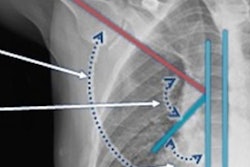

John Sabol, PhD, a scientist at Konica Minolta, described a deep-learning (DL) algorithm designed to measure what’s known as the scapulohumeral rhythm (SHR) of the shoulder. The SHR is the motion between the scapula and the humerus, and visualizing this motion can provide insights into pathology of injuries such as rotator cuff tears, Sabol noted.

DDR is an emerging imaging technique that uses a pulsed x-ray source to acquire a series of radiographs at six to 15 frames per second. These images are then processed to visualize joints in motion. The technology has been applied to several thoracic and musculoskeletal imaging applications and notably has previously been used to visualize the SHR.

In this study, the goal was to develop a DL algorithm that can automatically determine the SHR, which normally requires complex and time-consuming manual calculations by clinicians and thus is rarely performed in routine clinical cases, he said.

The prototype DL algorithm was trained on 447 images from 267 cases to recognize the humerus and scapula positions, calculate the required scapulothoracic and glenohumeral angles, and thus determine the SHR across the complete range of abduction.